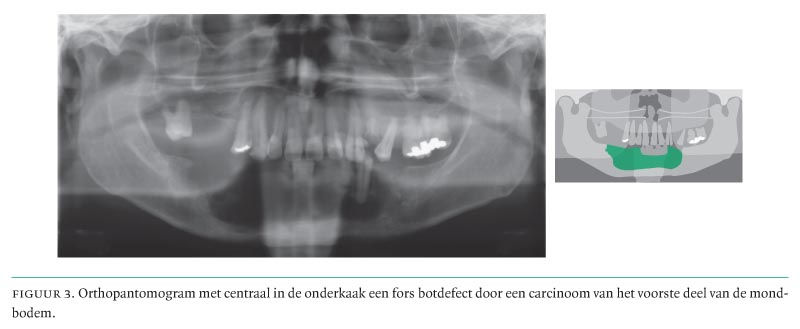

- Bij de diagnostiek van de primaire tumor en de hals wordt naast een zorgvuldig klinisch onderzoek gebruikgemaakt van echografie, vaak gecombineerd met cytologische punctie, MRI en CT, en voor de botinvasie van de onderkaak technetiumscintigrafie in combinatie met een orthopantomogram.